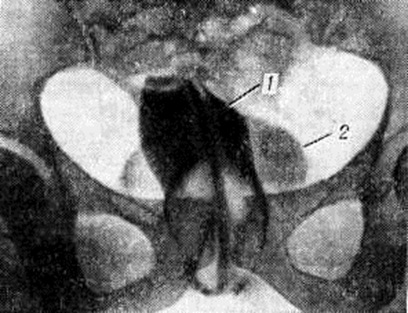

Исследование прямой кишки (смотри полный свод знаний Ректороманоскопия), уретроскопия (смотри полный свод знаний) и особенно уретрография, при которой удаётся выявить изменения уретры и затёк контрастного вещества в прямую кишку, подтверждают диагноз (рисунок 2). Изредка уретропростаторектальные свищи закрываются самостоятельно при проведении активной антибактериальной терапии, например, после абсцессов предстательной железы и пролежней при камнях уретры. Оперативное лечение их многоэтапное. Вначале производят цистостомию и наложение противоестественного заднего прохода, затем по стихании воспалительного процесса приступают к основному этапу — закрытию свища. Используют промежностный, брюшно-промежностный и трансректальный доступы. Успеху операции способствуют широкое иссечение свищевого хода и окружающей его рубцовой ткани, мобилизация прямой кишки и уретры для смещения на разные уровни мочевого и калового отрезков свища, раздельное ушивание прямой кишки и уретры, а также использование лоскута из мышечной ткани, вводимого между мочевым пузырём и прямой кишкой. Применяют лоскуты на ножке из большой ягодичной мышцы, нежной мышцы бедра или волокна мышцы, поднимающей задний проход. При успехе операции через 2—3 месяцев удаляют дренаж из мочевого пузыря, а затем восстанавливают проходимость кишечника.

Рис. 3. | ||